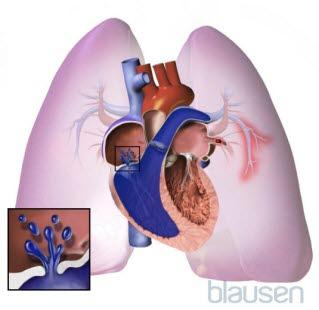

Cor pulmonaleLungekretsløpet går fra høyre hjertekammer og ut i lungene via lungepulsårene, og videre til hårrørsårene i lungevevet. Samleårer (vener) fører så blodet tilbake til venstre forkammer i hjertet. Det er høyre hjertekammer som pumper blodet ut i lungekretsløpet. Venstre hjertekammer pumper blodet ut i det store kretsløpet. De aller fleste tilfeller av hjertesvikt skyldes svikt i venstre hjertekammer, sjeldnere oppstår svikt i høyre hjertekammer.

Langvarig høyt blodtrykk i lungekretsløpet fører til utvikling av en tilstand som kalles cor pulmonale (cor = hjerte, pulmonal = som har med lungene å gjøre). Det er en tilstand der høyre hjertekammer blir forstørret fordi denne delen av hjertet må utvikle økt kraft for å klare å drive blodet gjennom lungekretsløpet. Cor pulmonale kan oppstå både akutt og kronisk.

Animasjon av høyt blodtrykk i lungekretsløpet